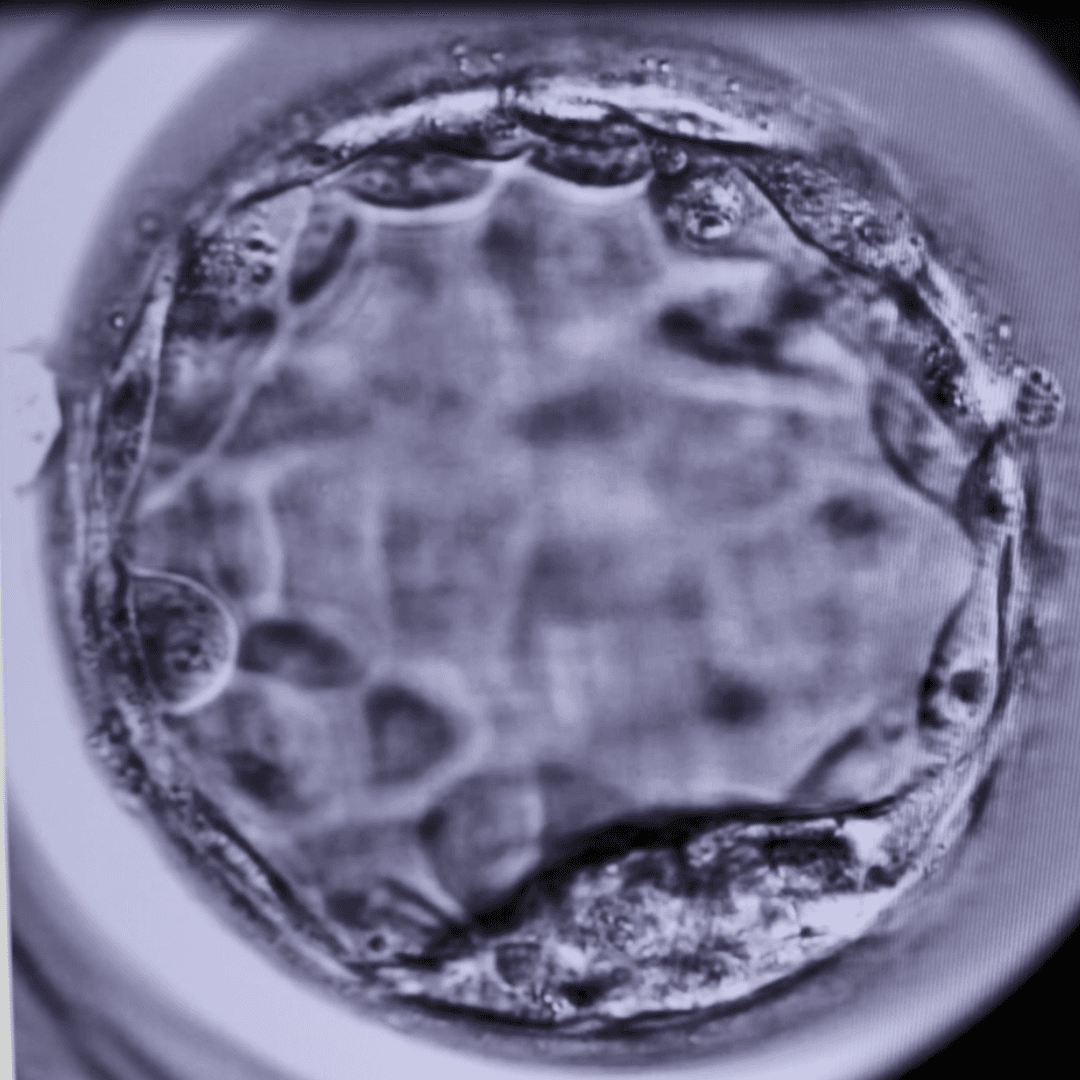

Image: Image of a blastocyst in the human body. Image supplied